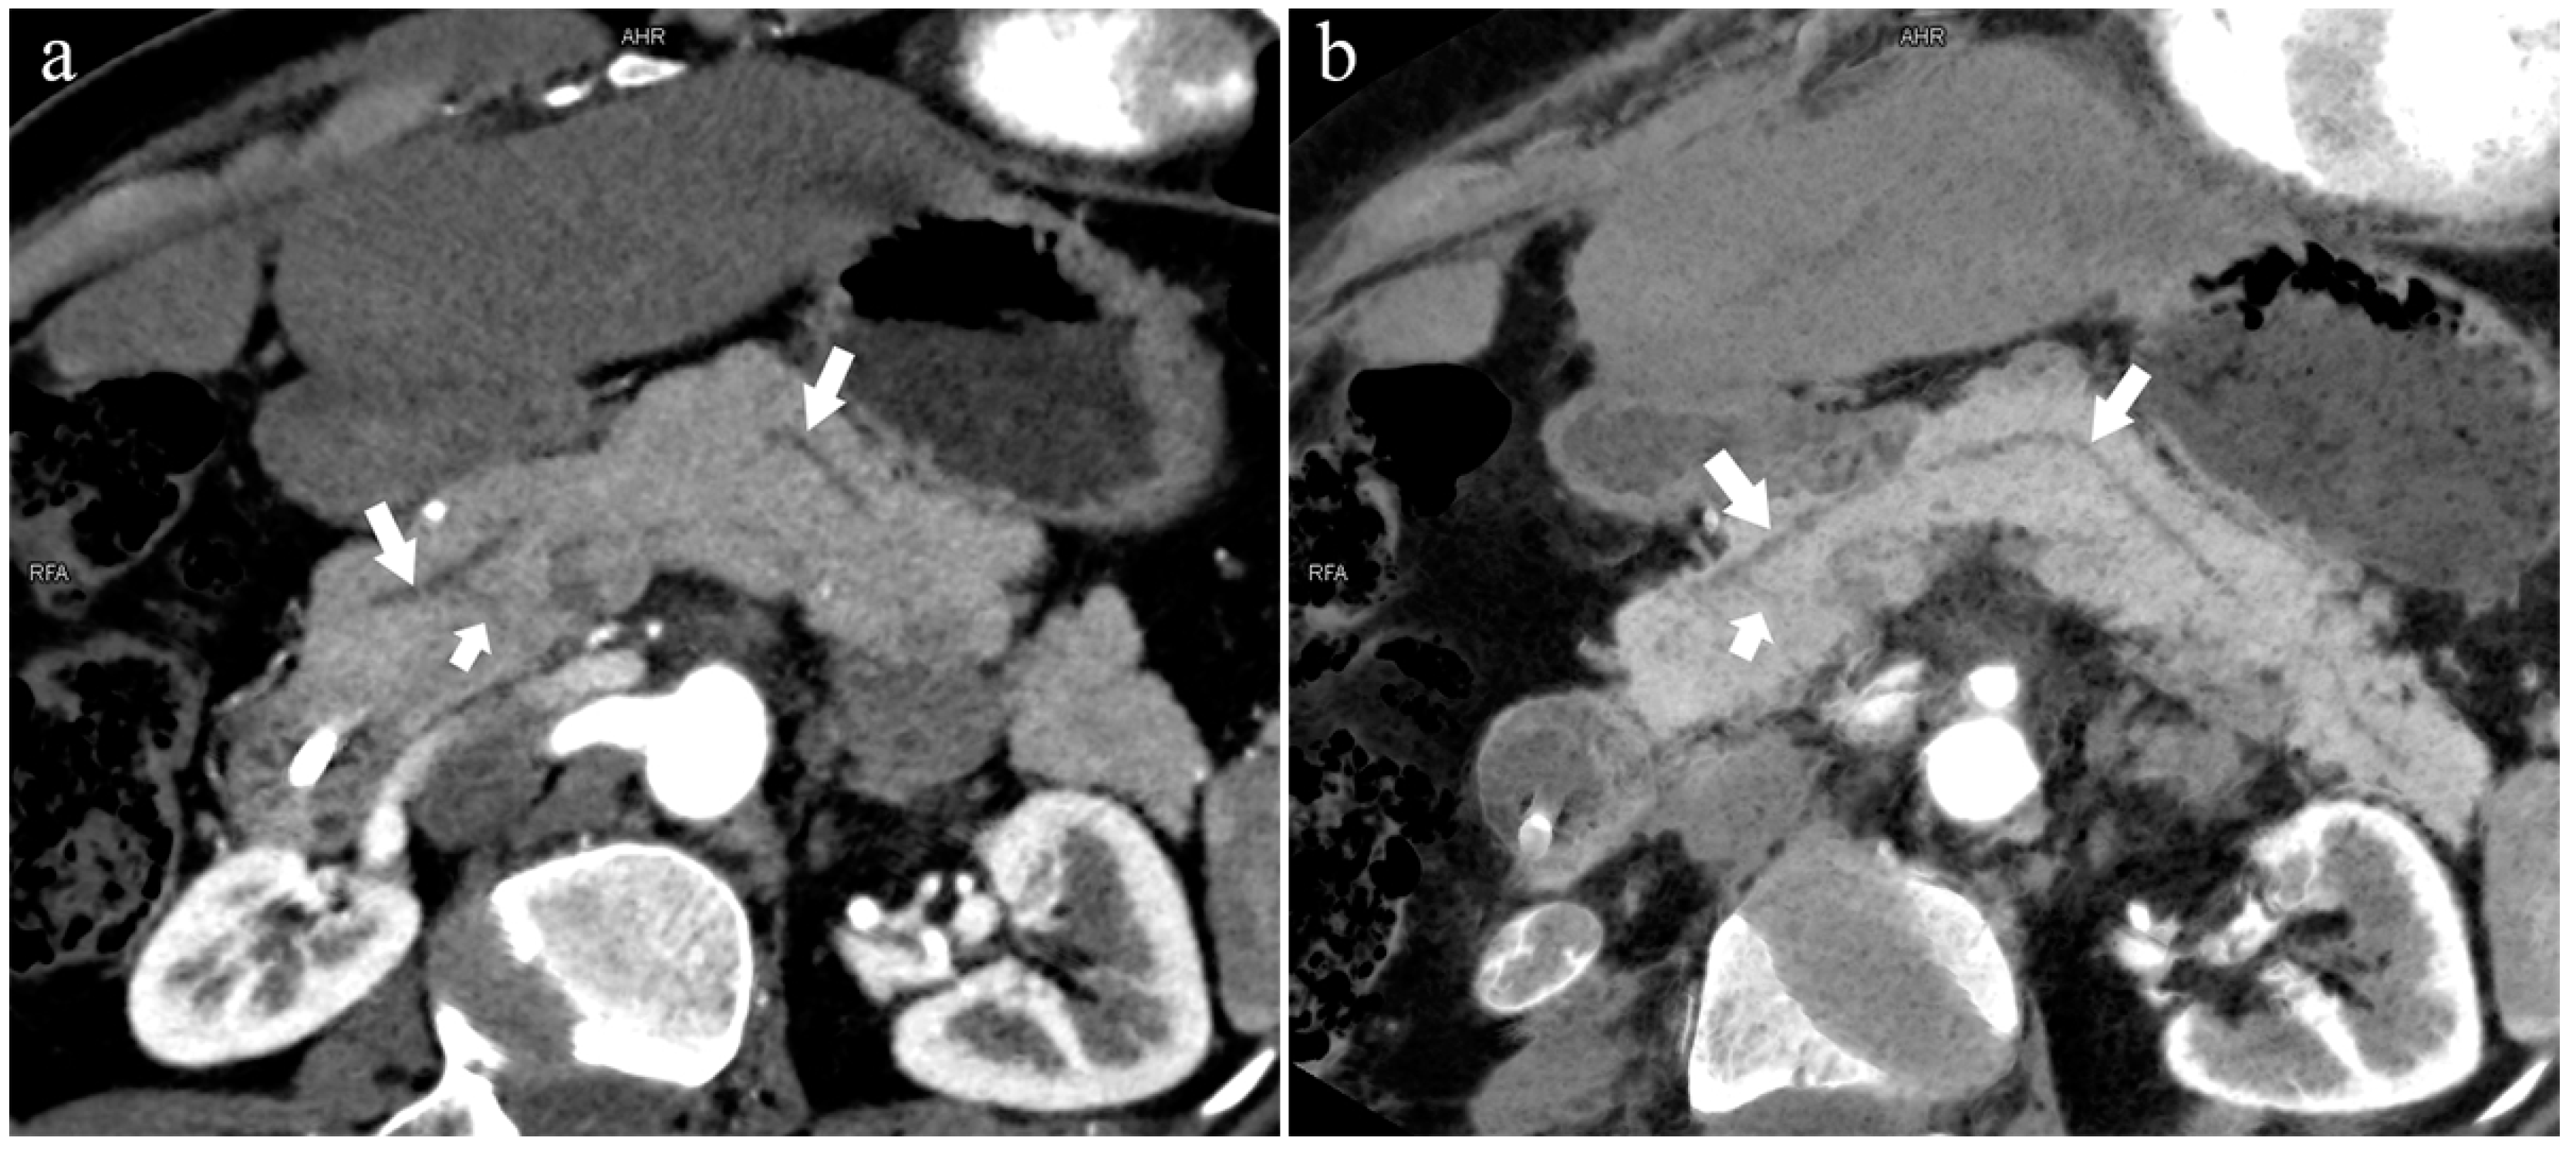

There were 121 patients with AP in the two groups. In the variant group, a total of 27 patients had AP (22%, 27/121), of which the incidence of type 3c (33.3%, 9/27) and type 4a (18.5%, 5/27) are higher. There were 18 patients with CP, of which six patients (33%, 6/18) were in the variant group. Patients with autoimmune pancreatitis (AIP) only existed in the normal group (n = 4).

As shown in Table 2, there were no statistical differences between the normal and variant groups in terms of PC, other pancreatic tumors, and AC. The distributions of the AP (p = 0.002), CP (p = 0.025), and DPC (p = 0.020) were significantly different in the normal and variant groups, respectively. In Table 3, except for patients with type 3c who had a correlation with AP (p = 0.014), there were significant differences between type 4a and AP, CP (p = 0.024, 0.025, respectively).

In the 852 patients, there was a significant difference between the low-keV DECT and MRCP images in observing the pancreatic duct system (p < 0.05), and the mean rank of the former was higher than that of the latter (909.44 > 795.56). Thus, the sharpness of the pancreatic duct images of low-keV DECT is better than that of MRCP. Figure 6 shows that the reconstructed DECT images (MIP and MinIP, 45 keV) could show small ADP (Figure 6a,b), while this was not observed on MRCP (Figure 6c).

5.3.2. Pancreatitis

Kensuke Takuma et al. [27] suggested that complete PD may be the etiology of AP, CP, and dorsal pancreatic cancer. An important factor of complete PD promoting these diseases is dorsal pancreatic duct obstruction. We considered that, in type 4, only the dorsal pancreatic duct drains the pancreatic juice to the MiP. However, the MiP easily accumulates and stagnates due to the small physiological opening, which may lead to pancreatitis [40,41]. In this study, there were significant differences between AP (Figure 4), CP, and complete PD.

In the variant group, the incidence of AP in patients with type 3c was considerably higher than that in type 3a. Type 3c, also known as “reverse pancreas divisum”, does not communicate with the MPD but is open to the MiP, while type 3a is the opposite. In type 3c, there is a “vacuum” area between the MPD and ADP that may not be communicated, while type 3a cannot be drained directly by the MiP, but most areas can be drained indirectly by entering the MPD. This may be a reasonable explanation for this phenomenon. Table 4 also confirms our point of view. The frequency of type 2 was 2.4%, and AP accounted for 26% of type 2, which may have also been caused by the small orifice of the MiP drainage and the poor secretion flow [40,41].